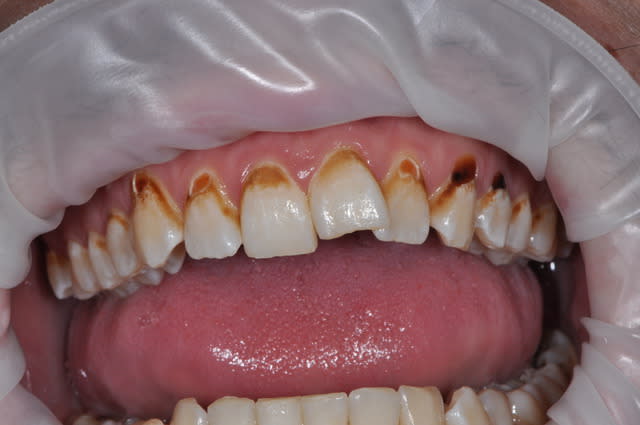

pour vous c'est du à quoi ces altérations des collets ??

Ca ressemble beaucoup plus à des caries rampantes du confiseur, du coca addict ou même du biberon.

+ une érosion mécanique genre syndome bruxisme + brosse à dent passée à la va-vite, bien horizontalement, bien fort.

Si on ajoute à ça le chômage (gros consommateurs des sucreries, les chômeurs, c'est à peu près les seuls plaisirs qu'ils peuvent s'offrir).

Donc sodas+ bonbons + brossage iatrogène + tabac/café pour les colorations, c'est le cocktail sur lequel je parie. Tiens nous au jus (sans sucre)!

Je mise sur des sodas, avec tabac.

J'ai eu un jeune de 17 ans l'autre jour, qui avait toutes ses dents cariées au collet, comme sur cette photo, mais sans cette coloration très orangée. Je l'avais vu 2 ans avant : 1 carie occ sur 36, rien d'autre. Sinon, son hygiène était OK.

C'est donc certainement une drogue qui est responsable de ce genre de déminéralisations...après, il ya drogues dures, et drogues tout court...

La première chose à laquelle j'ai pensé en voyant la photo:

http://en.wikipedia.org/wiki/Meth_mouth

Oui , je suis assez d' accord avec vos hypothèses à tous : coca , drogue , carie du pâtissier ou mangeur de chocalatines...!

La seule chose qui m' intrigue , c'est que l' atteinte des collets soit plus prononcée d' un côté , comme un suceur de sucettes-boules ( comme Laurent Blanc ...!) qui garderait , longtemps , sa sucette-bonbon dans la bouche et toujours du même coté !